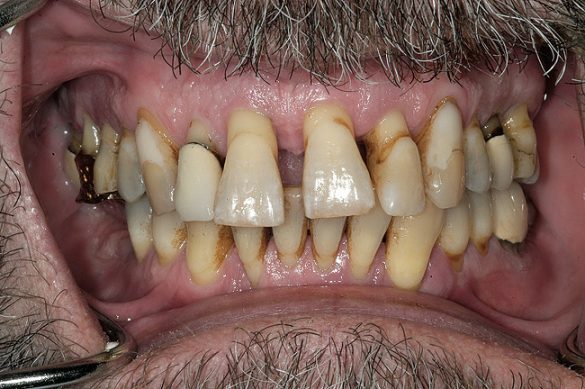

Examinarea a evidenţiat adâncimi de sondare generalizate cuprinse între 5-9mm, cu sângerare generalizată şi locaţii cu supuraţie. Combinaţia recesiunii cu adâncimile de sondare a generat o pierdere de ataşament generalizată cu valori între 8-12mm. Radiografiile au evidenţiat pierdere osoasă orizontală severă, defecte osoase verticale multiple şi aspectul unei posibile comunicări parodontale apicale. Aproximativ jumătate dintre dinţi prezentau mobilitate de clasa I, cu dinţii restanţi având o mobilitate de clasa a 2-a şi a 3-a. Toţi molarii manifestau cel puţin o invazie de furcaţie de gradul 1, cu multiple implicări de gradul 2 şi 3. Diagnosticul s-a stabilit a fi AAP tip IV, parodontită avansată.

La examinarea clinică, o serie de dinţi prezentau restaurări directe mici acceptabile. Dinţii de la 1.7. la 1.4., de la 1.2. la 2.6., 3.6. şi 4.5. prezentau fie restaurări directe voluminoase, fie coroane cu acoperire totală, cu un grad ridicat de compromitere structurală. Nu s-au identificat leziuni carioase active. Implicarea pulpară era vizibilă la nivelul molarului 3.6.

Pacientul a relatat o tendinţă ocazională de bruxism. Examinarea a evidenţiat sensibilitatea musculaturii masticatorii şi crepitaţii la nivelul ATM. Era prezentă atriţia minimă la toţi dinţii frontali. Dinţii frontali erau în contact, iar dinţii maxilari frontali era evazaţi şi mobili. Istoricul pacientului privind bruxismul, alături de crepitaţii şi sensibilitatea musculară a contribuit la diagnosticul disfuncţiei ocluzale.

La examinare s-au obiectivat: dinamică labială maxilară crescută, cu afişarea în repaus a 3-4mm din incisivi. La zâmbetul total, marginile gingivale libere nu erau vizibile, datorită recesiunii, dar 2-4mm din structura radiculară era vizibilă dincolo de joncţiunea smalţ-cement (CEJ) la toţi dinţii superiori. Festonul ţesutului moale era apropiat de normal, însă părea neatractiv datorită gradului mare de recesie şi a pierderii papilei. În regiunea frontală inferioară s-a remarcat asimetria orizontală (fig. 2).